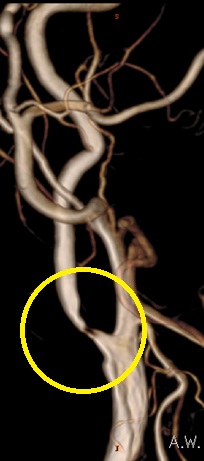

狭窄の程度が強くなると、その後の脳梗塞を予防するために観血的手術である頸動脈内膜剥離術もしくは脳血管内治療である頚動脈ステント留置術が必要となります。高齢化が進み麻酔をかけるリスクが高い患者様に対しては侵襲度の低い頚動脈ステント留置術を積極的に行っております。

頸動脈ステント留置術(CAS)

ステント治療前 |

ステント治療後 |